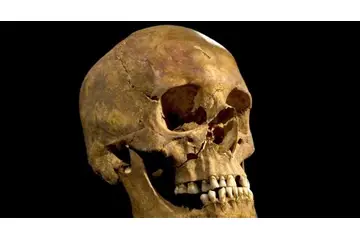

- Deformiteler: Uzun süreli kemik hastalıkları, deformitelere yol açabilir. Özellikle osteoporoz gibi durumlarda kemik yapısında zayıflama görülebilir.

- Kırıklar: Osteoporoz gibi hastalıklar, kemiklerin kırılma riskini artırır. Özellikle yaşlı bireylerde bu durum sık görülmektedir.